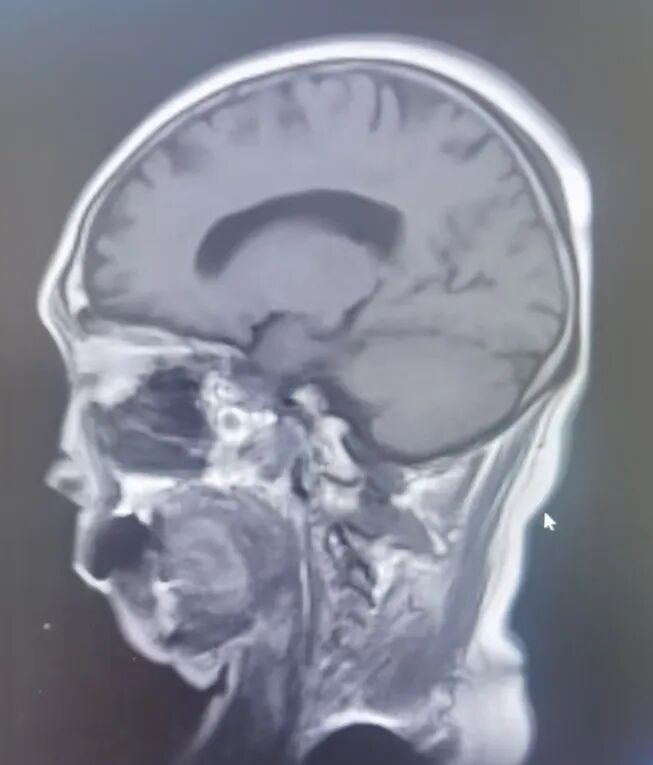

原来,李先生的母亲今年72岁,家住龙口市,一年前在当地医院查体,发现左侧桥小脑角区占位病变,诊断为“听神经瘤”,肿瘤小于2cm,医生建议观察1年后复查。1月前,老人出现了左耳听力下降的临床症状,复查颅脑核磁发现肿瘤有明显生长!

因肿瘤起源于神经的鞘膜,压迫面听神经,术中保留面听神经功能显得尤为重要。手术由耿素民教授亲自主刀,在我院神经外科团队的配合下,术中应用显微镜和神经内镜双镜联合辅助,不磨除内听道骨质便成功将肿瘤全部切除,并完好保留了面听神经功能。

应用双镜联合显微手术切除听神经瘤的优势为: 1.在不磨除内听道情况下,应用神经内镜可观察内听道内全部肿瘤,避免了手术盲区;

3.切除肿瘤后可观察内听道全程情况,避免肿瘤残留,更好地辨认神经走行;

4.避免在磨除内听道后唇时因颈静脉球高位出血风险,以及术后脑脊液漏的风险。